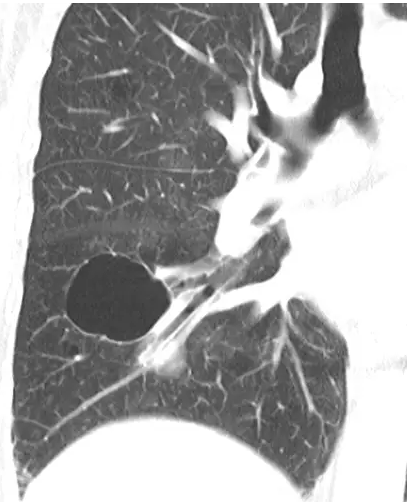

胸片和CT表现

囊肿表现为圆形的肺实质透亮区或低密度区,与正常肺组织分界清楚。囊壁厚薄不一,但通常壁薄(<2 mm),且不伴有肺气肿

(图2)。肺里的囊肿通常含空气,但偶然也含有液体或固体物质。囊变这个词,常用作描述淋巴管平滑肌瘤病或朗罕氏细胞增多症患者肺内的增大的薄壁含气腔,壁较厚的蜂窝样囊状病变见于肺纤维化

末期患者。

图2 CT显示肺囊肿